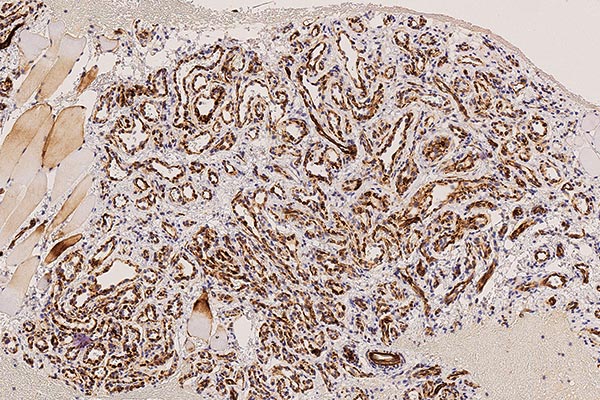

In der 130-fachen Vergrößerung (immunhistochemische CD31-Färbung zur Darstellung von Gefäßendothelien) zeigt sich eine intensive braune Anfärbung der endothelialen Strukturen. Dies beweist den Gefäßcharakter der Läsion. Die Gefäße sind beim infantilen Hämangiom als vaskulärer Tumor typisch lobuliert angeordnet.